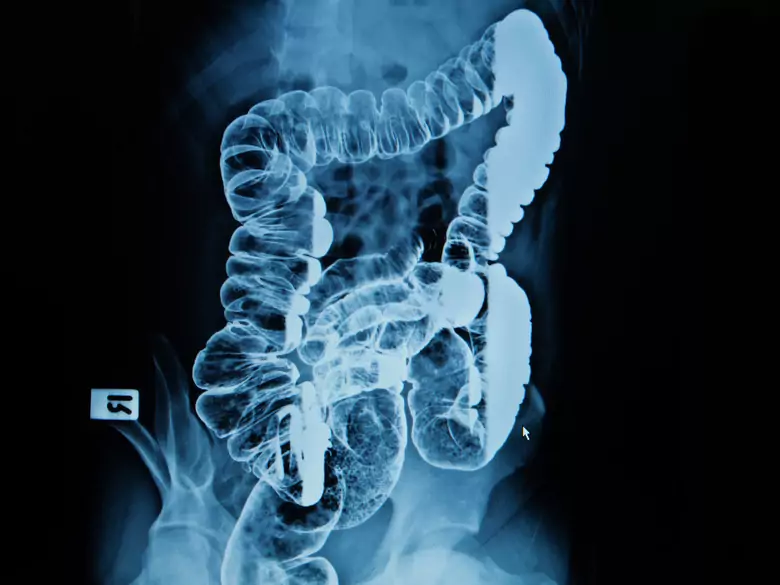

Examen intestinal